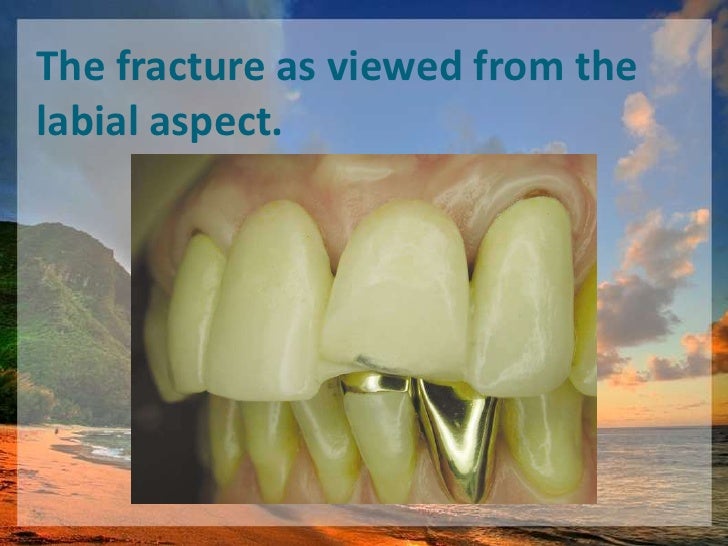

Repairing Fractured Pfm | PPT

Repairing Fractured Pfm

Repairing Fractured Pfm

Repairing Fractured Pfm

Repairing Fractured Pfm

Repairing Fractured Pfm